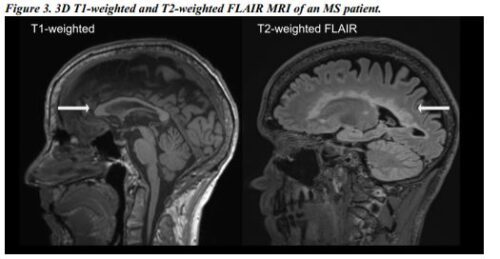

T1 の IRM ポンダーダス

複数の硬化症に関する実際の IRM に関する情報を調べます。ラス IRM は、T1 の炎症活動領域を調査し、新しい病変を代表するものです。複数の硬化症診断を行う際に、詳細な診断情報を提供します。

T1 の IRM ポンダーダは、「黒人アグヘロス」と呼ばれるセレブリティの永久的な滞在期間です。

新しい病変を拡張し、IRM ポンデラーダと T1 ポドリアン インディカル エル 進捗状況を拡張します。

T2 の IRM ポンダーダ

ラス IRM ポンダダスは、T2 病変と脊柱の特別な部分の病変を検出します。複数の硬化症の可能性があるかどうかを決定するための医療情報が提供されます。

T2 での IRM ポンデラーダでの硬化性硬化症の複数の病変。 T2 識別子と IRM の損傷により、T2 が重大な障害を引き起こす可能性があります。